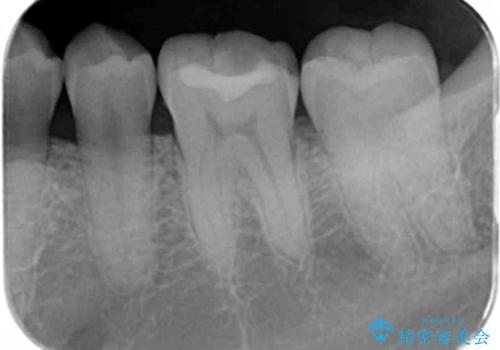

奥歯が欠けた セラミックインレーでの治療

- 奥歯が欠けたとのことで来院されました。

白い詰め物をご希望されたため、セラミックインレーでの治療を行います。

治療前後で比べると、詰め物と歯の間のすき間もなくなりセラミックインレーの適合の良さが伺えます。